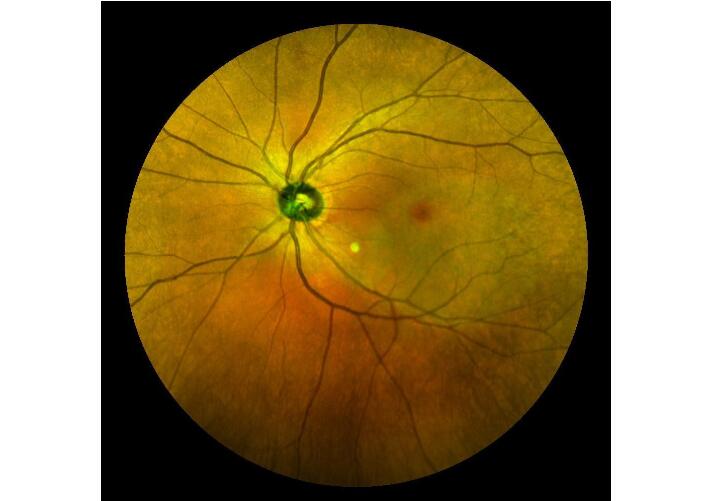

| 6 |  | Laser multicolor image of fundus (Multicolor) | Laser multicolor image has more diagnostic value for a variety of fundus diseases including DR, and it can be used more clearly for image with small pupil and turbidity of dioptric media |

Cases

Retina Angiograph Digital 160° Ophthalmic Equipment Images |